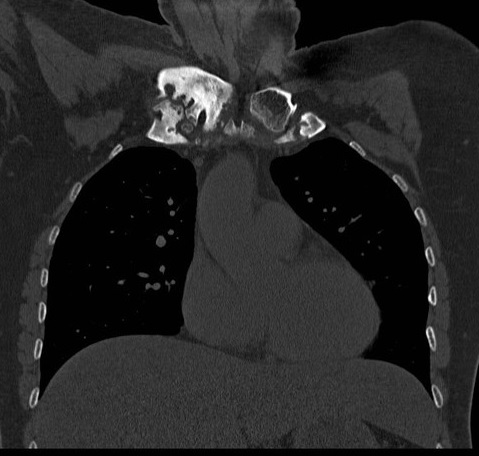

Même cas en coupe TDM coronal

( frontal ) avec image de

oedème de la moelle

osseuse dans sous-chondral gauche et élargissement et

épaississement du cartilage de articulation manubrium -costale

gauche etr en vue très nette |